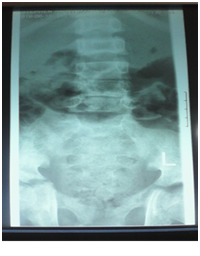

A 12-year-old boy was diagnosed with Sickle Cell Disease (SCD) with genotype SS about one year prior to. He presented with 2 months history of inability to walk and pain in both legs to Komfo Anokye Teaching Hospital in Kumasi, Ghana. The complaints were associated with marked weight loss and generalized body pain. He had been admitted about 2 weeks prior to the onset of current symptoms on account of abdominal pain and anaemia where he was haemo-transfused, given medications and subsequently discharged. There were no other significant findings in the past medical history, immunization history, nutritional and developmental histories. On examination he was found to be wasted (Weight for Height z-score <-3SD), pale, afebrile and anicteric. He had palpable axillary and inguinal lymph nodes (each measuring about 1cm to 1.5cm, mobile, non-tender and not matted). Vital signs were normal on admission. Other significant examination findings were obvious swelling of the right leg which was warm to touch, erythematous and tender on palpation. He had a gibbus deformity of the lower thoracic spine with no remarkable neurological findings in the lower limbs. A diagnosis of SCD with vaso-occlusive crises and cellulitis of the right leg was made with differential diagnosis of osteomyelitis, Deep Vein Thrombosis and Potts disease. Initial investigations revealed WBC of 13.51 X 109/dl with Neutrophils 8.83 (65.3%) Lymphocytes 4.27 (31.6%) and Monocytes 0.25(1.9%), Hemoglobin 7.1g/dl, MCV-70.7, MCH-22.4, Platelets: 538, ESR-117, INR-1.05, Prothrombin Time-14.3secs and blood sugar-6.5mmol/L. Malaria parasites were not seen on the blood smear and patient was negative for Retro-Viral Screen for HIV. Other investigations included Doppler Ultrasound, Chest X-ray, Pelvic x-ray, Thoraco-lumbo-sacral spine X-ray (Figure 1-10). Blood culture and sensitivity could not be done at the time of admission as microbiology service in the hospital had a brief logistic challenge. Radiological findings revealed the following: Reduction in the vertebral body heights of T7-T10 with associated reduction in the intervertebral disc spaces and crowding of the posterior ribs. A paravertebral soft tissue mass extending from T4 vertebral level to T11. Coarse trabeculation and sclerosis of the ribs noted. Expansion of the anterior end of the left 8th rib with ill-defined lytic areas. Buckling of the cortex of the lateral aspect of the left 9th rib, suggestive of a fracture. The imaged portion of the proximal humerus shows periarticular osteopenia. Also noted was relatively small left humeral head with left glenohumeral joint space. There are patchy homogenous opacities in both lung fields predominantly in the lower zones. There was associated silhouetting of the hemi diaphragms bilaterally and the cardiac shadow. There was generalized sclerosis of the imaged pelvic bones with coarsening of the trabeculae. The right femoral head was deformed and expanded with sclerosis and lytic areas within. There was associated narrowing of the right hip joint space. The left femoral head also showed patchy lucencies. No deformity of the left femoral head seen. The left hip joint space appeared normal. Also noted was fusion of the sacroiliac joints bilaterally. There was diffuse sclerosis of the imaged vertebrae with coarse trabeculae. The vertebral endplates of L1/L2 and L3/L4 showed sharp depression at the margins with a flat base centrally giving it the H shaped appearance. Also noted were ill-defined lytic areas in the L3 to L5 vertebrae with associated end plate irregularities and reduced intervertebral disc spaces at L3/L4 and L4/L5. No paravertebral soft tissue mass seen. No fracture or listhesis seen. Changes of the thoracic spine were described under the chest x-ray.

These radiological diagnostic features were suggestive of sickle cell disease with Thoracolumbar spondylodiscitis, likely pyogenic; Bilateral Avascular Necrosis of the femoral head (early on the left); Septic arthritis of the right hip and left shoulder joint; Osteomyelitis of the left 8th and 9th ribs. Doppler Ultrasound of the lower limb revealed the following: The right common femoral and superficial femoral veins were of normal lumen with good wall to wall compressibility, good colour doppler and spectral wave form properties. The right popliteal and posterior tibial veins however showed extensive echogenic intraluminal-filling defect with resultant loss of wall-to-wall compressibility (percentage stenosis 76%). The accompanying arteries were of normal size and caliber and showed good colour doppler and spectral properties. There was thickening of the subcutaneous tissue with dilated fluid channels seen in the right foot. Inguinal as well as popliteal lymph nodes with retention of their fatty hilum noted averaging 0.9*0.5cm. Also noted was a 1.4*0.9*1.5cm (volume about 1.0ml) anechoic collection with low-level internal echoes at the medial aspect of the proximal thigh muscles; suggestive of inflammatory changes. Based on the Doppler findings a clinical diagnosis of Right Popliteal and Posterior Tibial Vein Thrombosis with Pyomyositis in a Sickle Cell Disease patient was considered and patient was subsequently administered subcutaneous Enoxaparin 40mg daily as well as Warfarin 3mg nocte, IV Clindamycin 150mg qid, IV Ciprofloxacin. After 2 days of Warfarin and Enoxaparin, INR and PT were repeated and results were 1.1 and 15.1s respectively. The child was followed up closely for four weeks and subsequently discharge. A repeat Doppler finding revealed a completely resolved thrombus with no evidence of DVT.